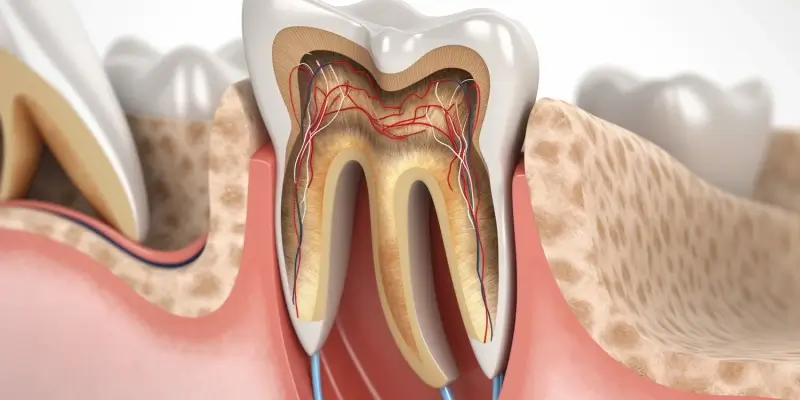

Lakowanie zębów to popularna metoda ochrony przed próchnicą, szczególnie w przypadku dzieci i młodzieży. Wiele osób zastanawia się jednak, czy ta procedura jest całkowicie bezpieczna. Lakowanie polega na nałożeniu specjalnego materiału na powierzchnię zębów, co ma na celu zabezpieczenie ich przed bakteriami i kwasami, które przyczyniają się do rozwoju próchnicy. Warto zauważyć, że materiały używane do lakowania są zazwyczaj bezpieczne i zatwierdzone przez odpowiednie instytucje zdrowotne. Niemniej jednak, jak każda procedura medyczna, lakowanie zębów wiąże się z pewnym ryzykiem. Możliwe skutki uboczne mogą obejmować reakcje alergiczne na składniki lakieru, a także problemy związane z niewłaściwym nałożeniem materiału. Dlatego ważne jest, aby zabieg był przeprowadzany przez wykwalifikowanego stomatologa, który oceni stan zębów pacjenta oraz dobierze odpowiedni materiał do lakowania.

Skuteczność lakowania zębów w zapobieganiu próchnicy jest jednym z najczęściej poruszanych tematów w kontekście tej procedury stomatologicznej. Lakowanie ma na celu zabezpieczenie bruzd i szczelin na powierzchni zębów, które są szczególnie narażone na gromadzenie się płytki bakteryjnej. Badania pokazują, że odpowiednio przeprowadzone lakowanie może znacząco zmniejszyć ryzyko wystąpienia ubytków, zwłaszcza u dzieci i młodzieży. Materiały używane do lakowania tworzą trwałą barierę, która chroni przed działaniem kwasów oraz bakterii, co jest kluczowe w walce z próchnicą. Warto jednak pamiętać, że lakowanie nie zastępuje codziennej higieny jamy ustnej, a jedynie ją wspiera. Regularne szczotkowanie zębów, nitkowanie oraz wizyty kontrolne u dentysty są niezbędne do utrzymania zdrowego uzębienia. W przypadku osób dorosłych, które mają już stałe zęby, lakowanie może być również korzystne, zwłaszcza jeśli mają one tendencję do występowania ubytków.

Materiały stosowane do lakowania zębów są kluczowym elementem skuteczności i bezpieczeństwa tego zabiegu. Najczęściej wykorzystywane są kompozyty żywiczne oraz materiały na bazie szkła jonomerowego. Kompozyty żywiczne charakteryzują się wysoką estetyką oraz dobrą przyczepnością do zęba, co sprawia, że są one popularnym wyborem wśród stomatologów. Z kolei materiały na bazie szkła jonomerowego mają zdolność uwalniania fluoru, co dodatkowo wspiera remineralizację szkliwa i zapobiega powstawaniu próchnicy. Wybór odpowiedniego materiału zależy od indywidualnych potrzeb pacjenta oraz lokalizacji zęba, który ma być zalakowany. Stomatolog oceni stan uzębienia i dobierze najlepsze rozwiązanie dla danego przypadku. Ważne jest również to, aby materiały były zatwierdzone przez odpowiednie instytucje zdrowotne, co zapewnia ich bezpieczeństwo i skuteczność.